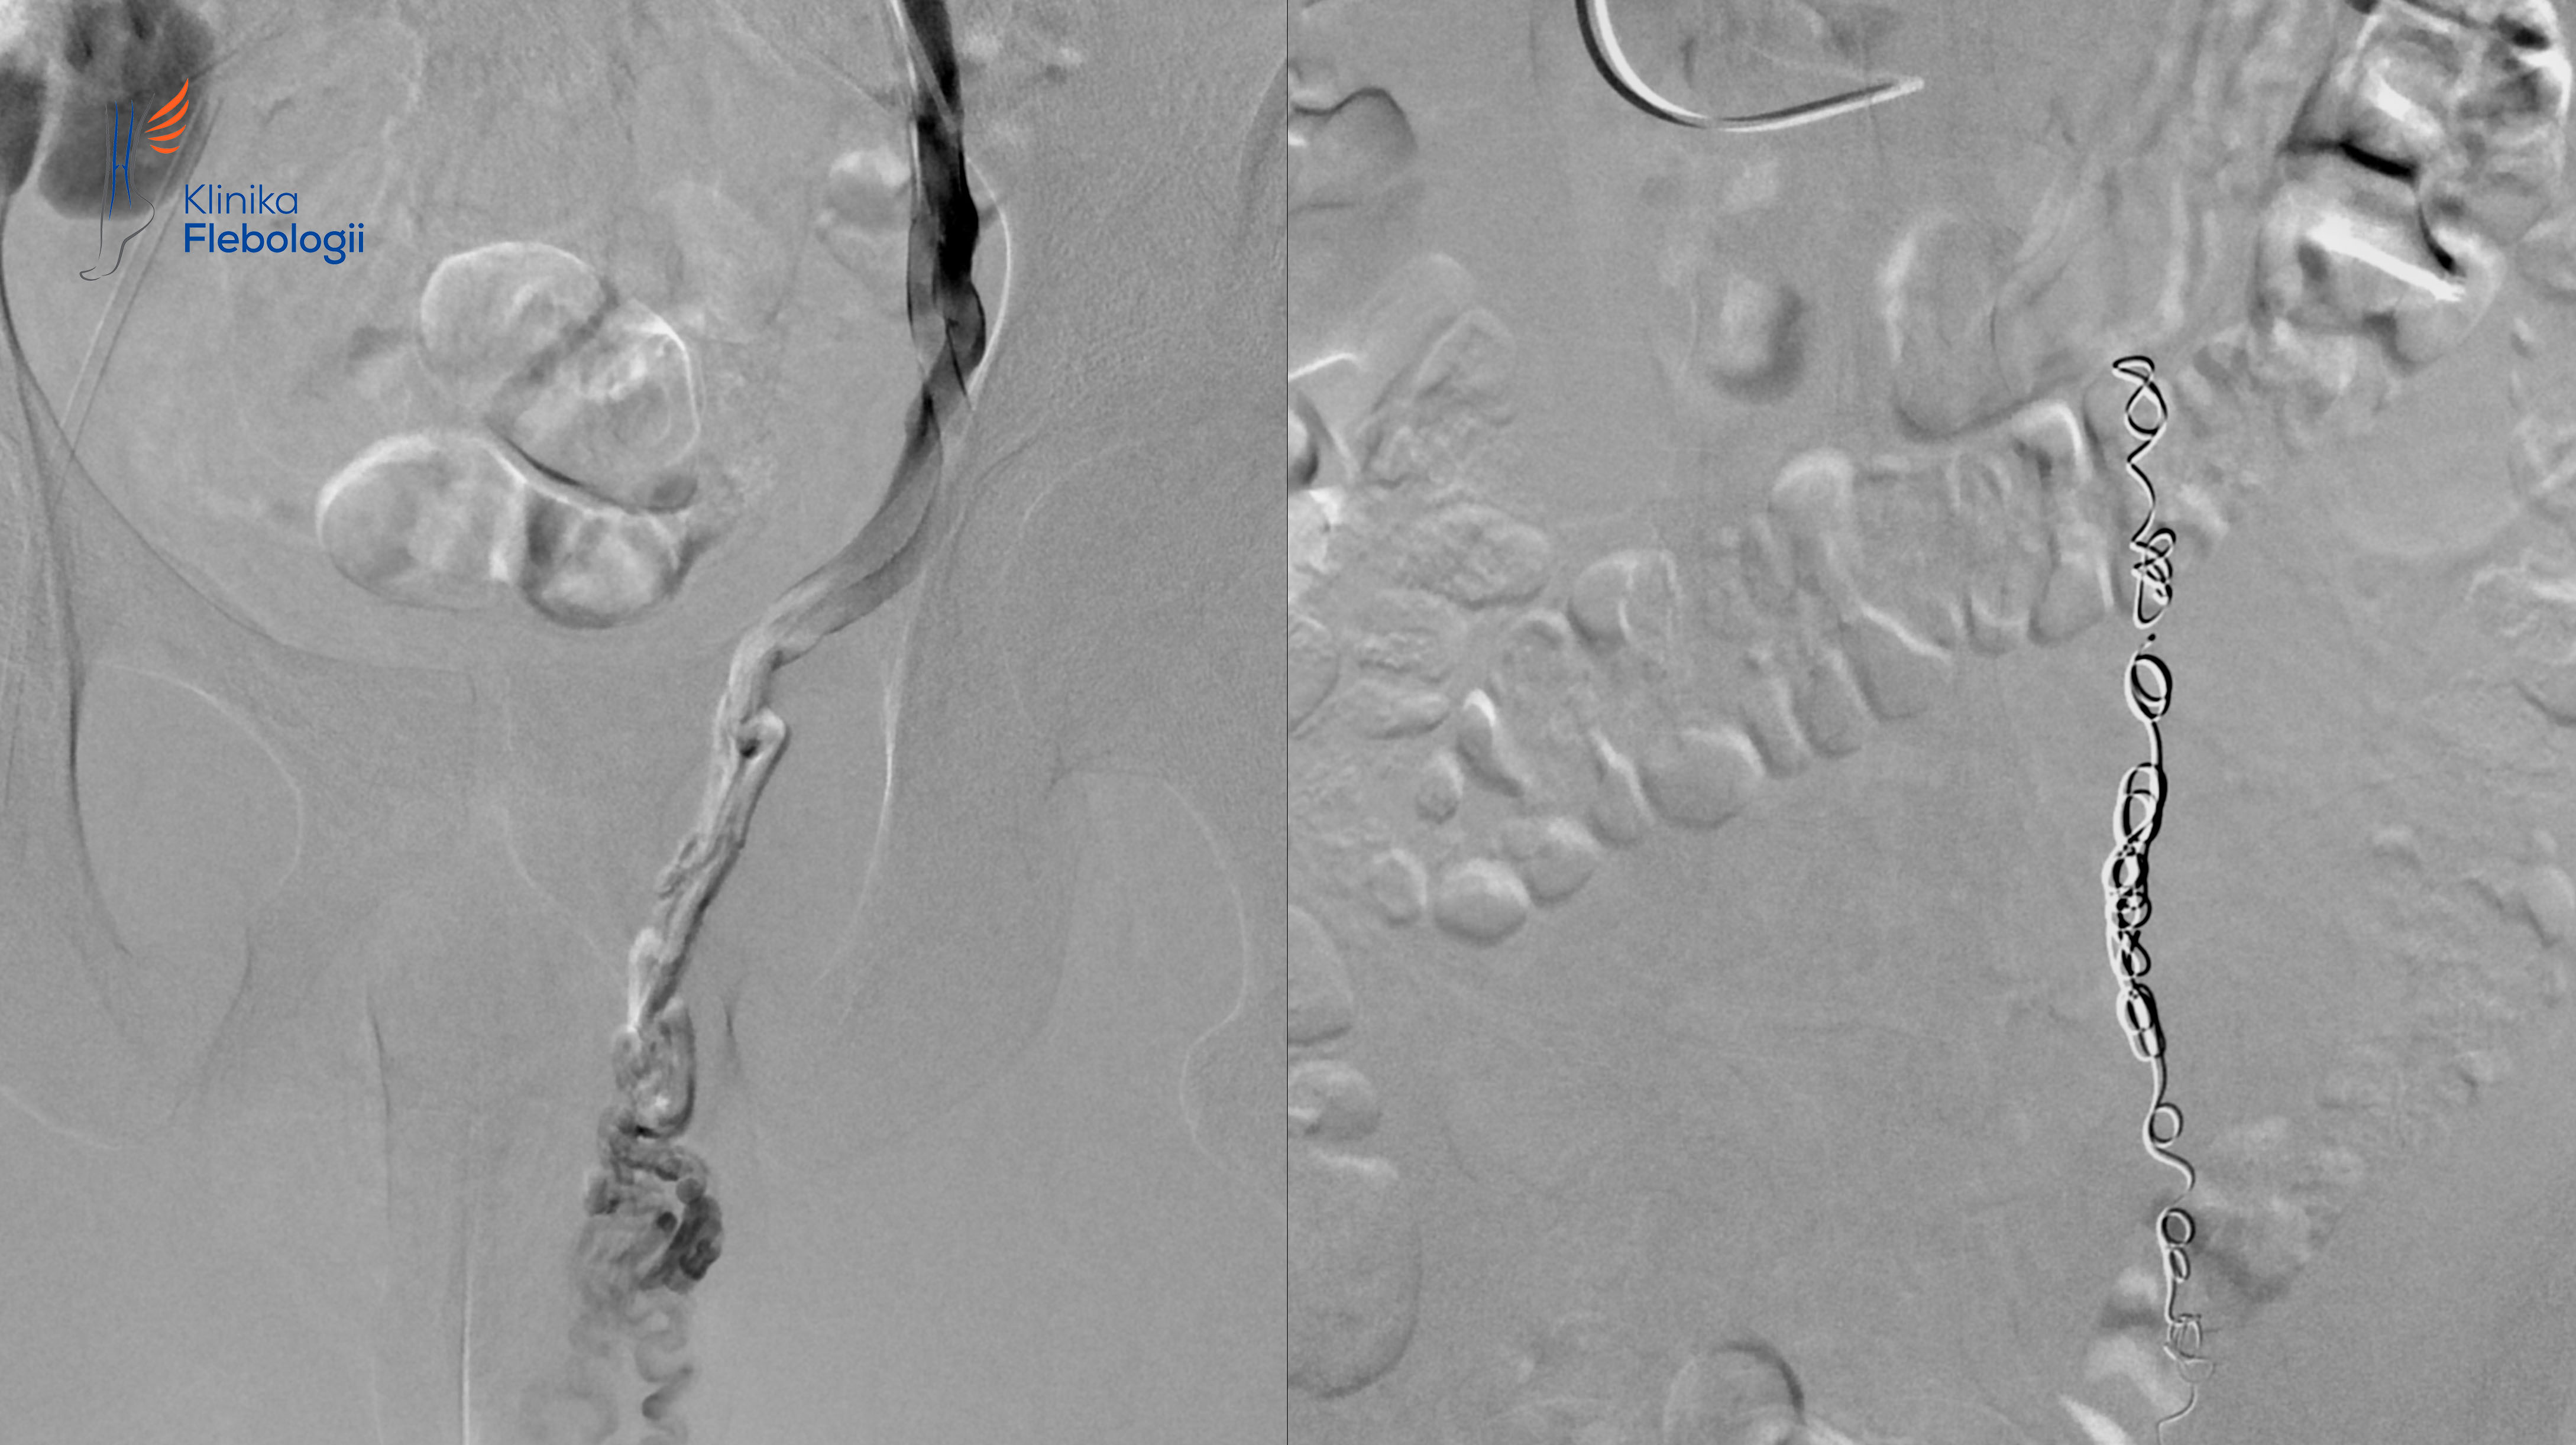

Zabieg embolizacji wewnątrzżylnej polega na zamykaniu niewydolnych żył przy użyciu specjalnych spiral z jednoczasową sklerotyzacją lub klejeniem poszerzonych splotów żylnych. W Klinice Flebologii w Warszawie leczone są również żylne przecieki kończynowe i żylaki atypowe na nogach, które często współtowarzyszą żylakom powrózka nasiennego.

Zabiegi embolizacji żylaków powrózka nasiennego wykonywane są w pracowni hemodynamiki Szpitala Medicover w Warszawie. Wszystkie zabiegi wykonywane są pod kontrolą sondy USG i z zastosowaniem cyfrowej aparatury angiograficznej. Procedury embolizacji żylnej przeprowadzone są w trybie 6-8 godzinnego przyjęcia do Szpitala, bez konieczności stosowania znieczulenia ogólnego. Pacjent w czasie zabiegu pozostaje w pełnym kontakcie z zespołem lekarsko-pielęgniarskim.

Pierwszy zabieg chirurgicznego zaopatrzenia żylaków powrózka został wykonany w roku 1952 przez Tullocha. Najnowsze podejście do leczenia tej przypadłości męskiej polega na przezskórnej embolizacji wewnątrzżylnej, czyli leczeniu przyczynowym skutkującym zamknięciem żyły jądrowej i niewydolnych naczyń żylnych splotu wiciowatego.

Jedynym sposobem przyczynowego leczenia w przypadku zespołów May-Thurnera czy zespołu dziadka do orzechów są metody wewnątrzżylne. Najbardziej skuteczne i najmniejinwazyjne ze wszystkich metod leczenia żylaków powrózka nasiennego są metody oparte na technice embolizacji wewnątrzżylnej, wykonywanej z niemalże bezbolesnego dostępu przezskórnego.

Metoda embolizacji wewnątrzżylnej pozwala w sposób wyjątkowo małoinwazyjny (niepotrzebne jest znieczulenie ogólne) i dokładny zamknąć, bez nacinania, źle działające naczynie żylne odpowiadające za refluks i tworzenie żylaków w obrębie worka mosznowego. Najczęściej zamykana jest lewa żyla jądrowa i jej odgałęzienia. Zabiegi wewnątrzżylne pozwalają wyleczyć również rzadsze przyczyny żylaków worka mosznowego, w przypadku których klasyczne podejście urologiczne jest nieskuteczne (około 20% pacjentów cierpiących na tę przypadłość).